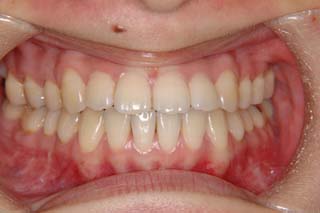

装置撤去です。動的処置は2年弱でしたので、通常のマルチブラケット治療とそれほど治療期間は変わりません。しかしながら、わずかな正中のズレが残ってしまいました。大きくは改善したのですが、左右のズレというものは、比較的、後戻りが現れやすい問題です。筋肉の影響によるものや、咬合平面の傾斜が左右的に水平でない事などが関係しているような気がします。今後は保定治療に移行し、数年にわたって咬合の安定状態を管理していきます。